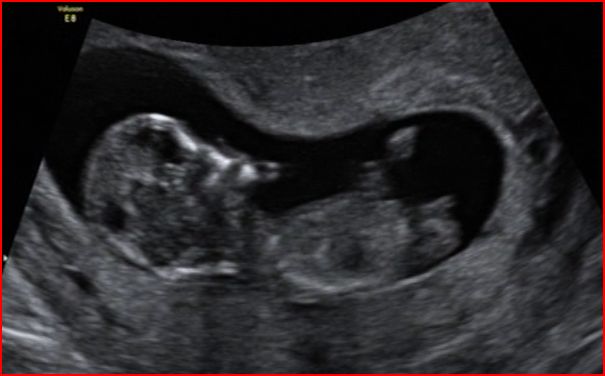

I have attached a copy of some stills from the dvd we have been given if anyone fancies a guess at the nub - first proper shot of baby is (by the us clock) ironically at 12:12 on the 12.12.2012.

Attachment 7239

Baby was 12+1 at the time of shots (hopefully, if everthing is ok and i haven't m/c'd before then from the cvs, i will post another one that i get from my 13 week nt scan on tuesday)